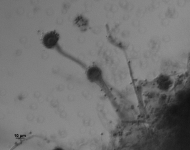

| Species Name: | Aspergillus fumigatus |

| Taxonomy: | FUNGI Ascomycota, Eurotiomycetes, Eurotiales, Aspergillaceae |

| Substrate: | skin, left ear canal; atypical showing greyish-white and blue-green sectors | Location: | CANADA Alberta, Edmonton (GEO: 53.544,-113.491) |

| Characters: | CULTURE CONDITIONS original culture slow growing and poorly sporulationg @ 25C, good growth at 37C - // MOLECULAR SYSTEMATICS Blast match 99-100% beta tubulin similarity with Aspergillus fumigatus - fide UAMH 2011 // THERMOTOLERANT - (Click for publications citing UAMH 625) |